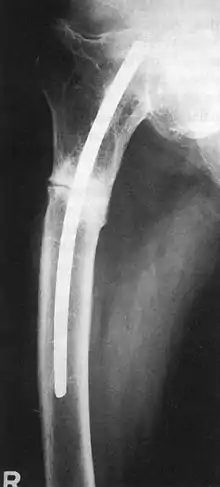

أجرى كونتشر ـ الذي كان أستاذاً بجامعة كييل[2] ـ أول عملية لتركيب مسماره النخاعي سنة 1939 في قسم الجراحة بمستشفى جامعة هامبورغ.[3] وقد قوبل مسمار كونتشر النخاعي في البداية بالرفض من جانب الجيش الألماني[3] وأيضاً من جانب جراح العظام الألماني الرائد لورنتس بوهلر (1885 ـ 1973) الذي انتقد هذا الابتكار بشدة[2]، فقام بين عامي 1943 و1944 بتعليم الجراحين الفنلنديين هذه التقنية خلال حرب لبلاند الفنلندية، مما تسبب في اعتراف زملائه من جراحي العظام بهذه التقنية على نطاق واسع بعد أن أثبتت نجاحها بالمقارنة بالتقنيات التقليدية التي كانت مستخدمة آنذاك[3]، ونظراً لظروف الحرب فقد حُرِمت طريقة كونتشر هذه من الخروج من ألمانيا واقتصر استخدامها ـ بعد الاعتراف بصلاحيتها ـ على الجيش الألماني الذي استخدمها بكثافة في علاج الجنود لإعادتهم إلى ميادين القياس في زمن قياسي للغاية مقارنة بالأساليب التقليدية التي سادت قبل استخدام مسمار كونتشر النخاعي. ولم يعرف العالم هذه التقنية بشكل واسع إلا عندما عاد أسرى الحرب الذين كانوا محتجزين في ألمانيا وفي أرجل بعضهم ذلك المسمار النخاعي المصنوع من الصلب.[3]

كان مسمار كونتشر قاسياً وكان شكل قطاعه العرضي مثلثاً وكان يستخدم للحفاظ على وضعية صحيحة للعظام المكسورة لحين التئامها.